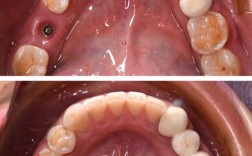

- 图片可能显示: 基台特写、不同材质的牙冠/桥模型、试戴牙冠、最终安装完成的种植牙(单颗、多颗或全口)效果对比图(术前 vs 术后)。